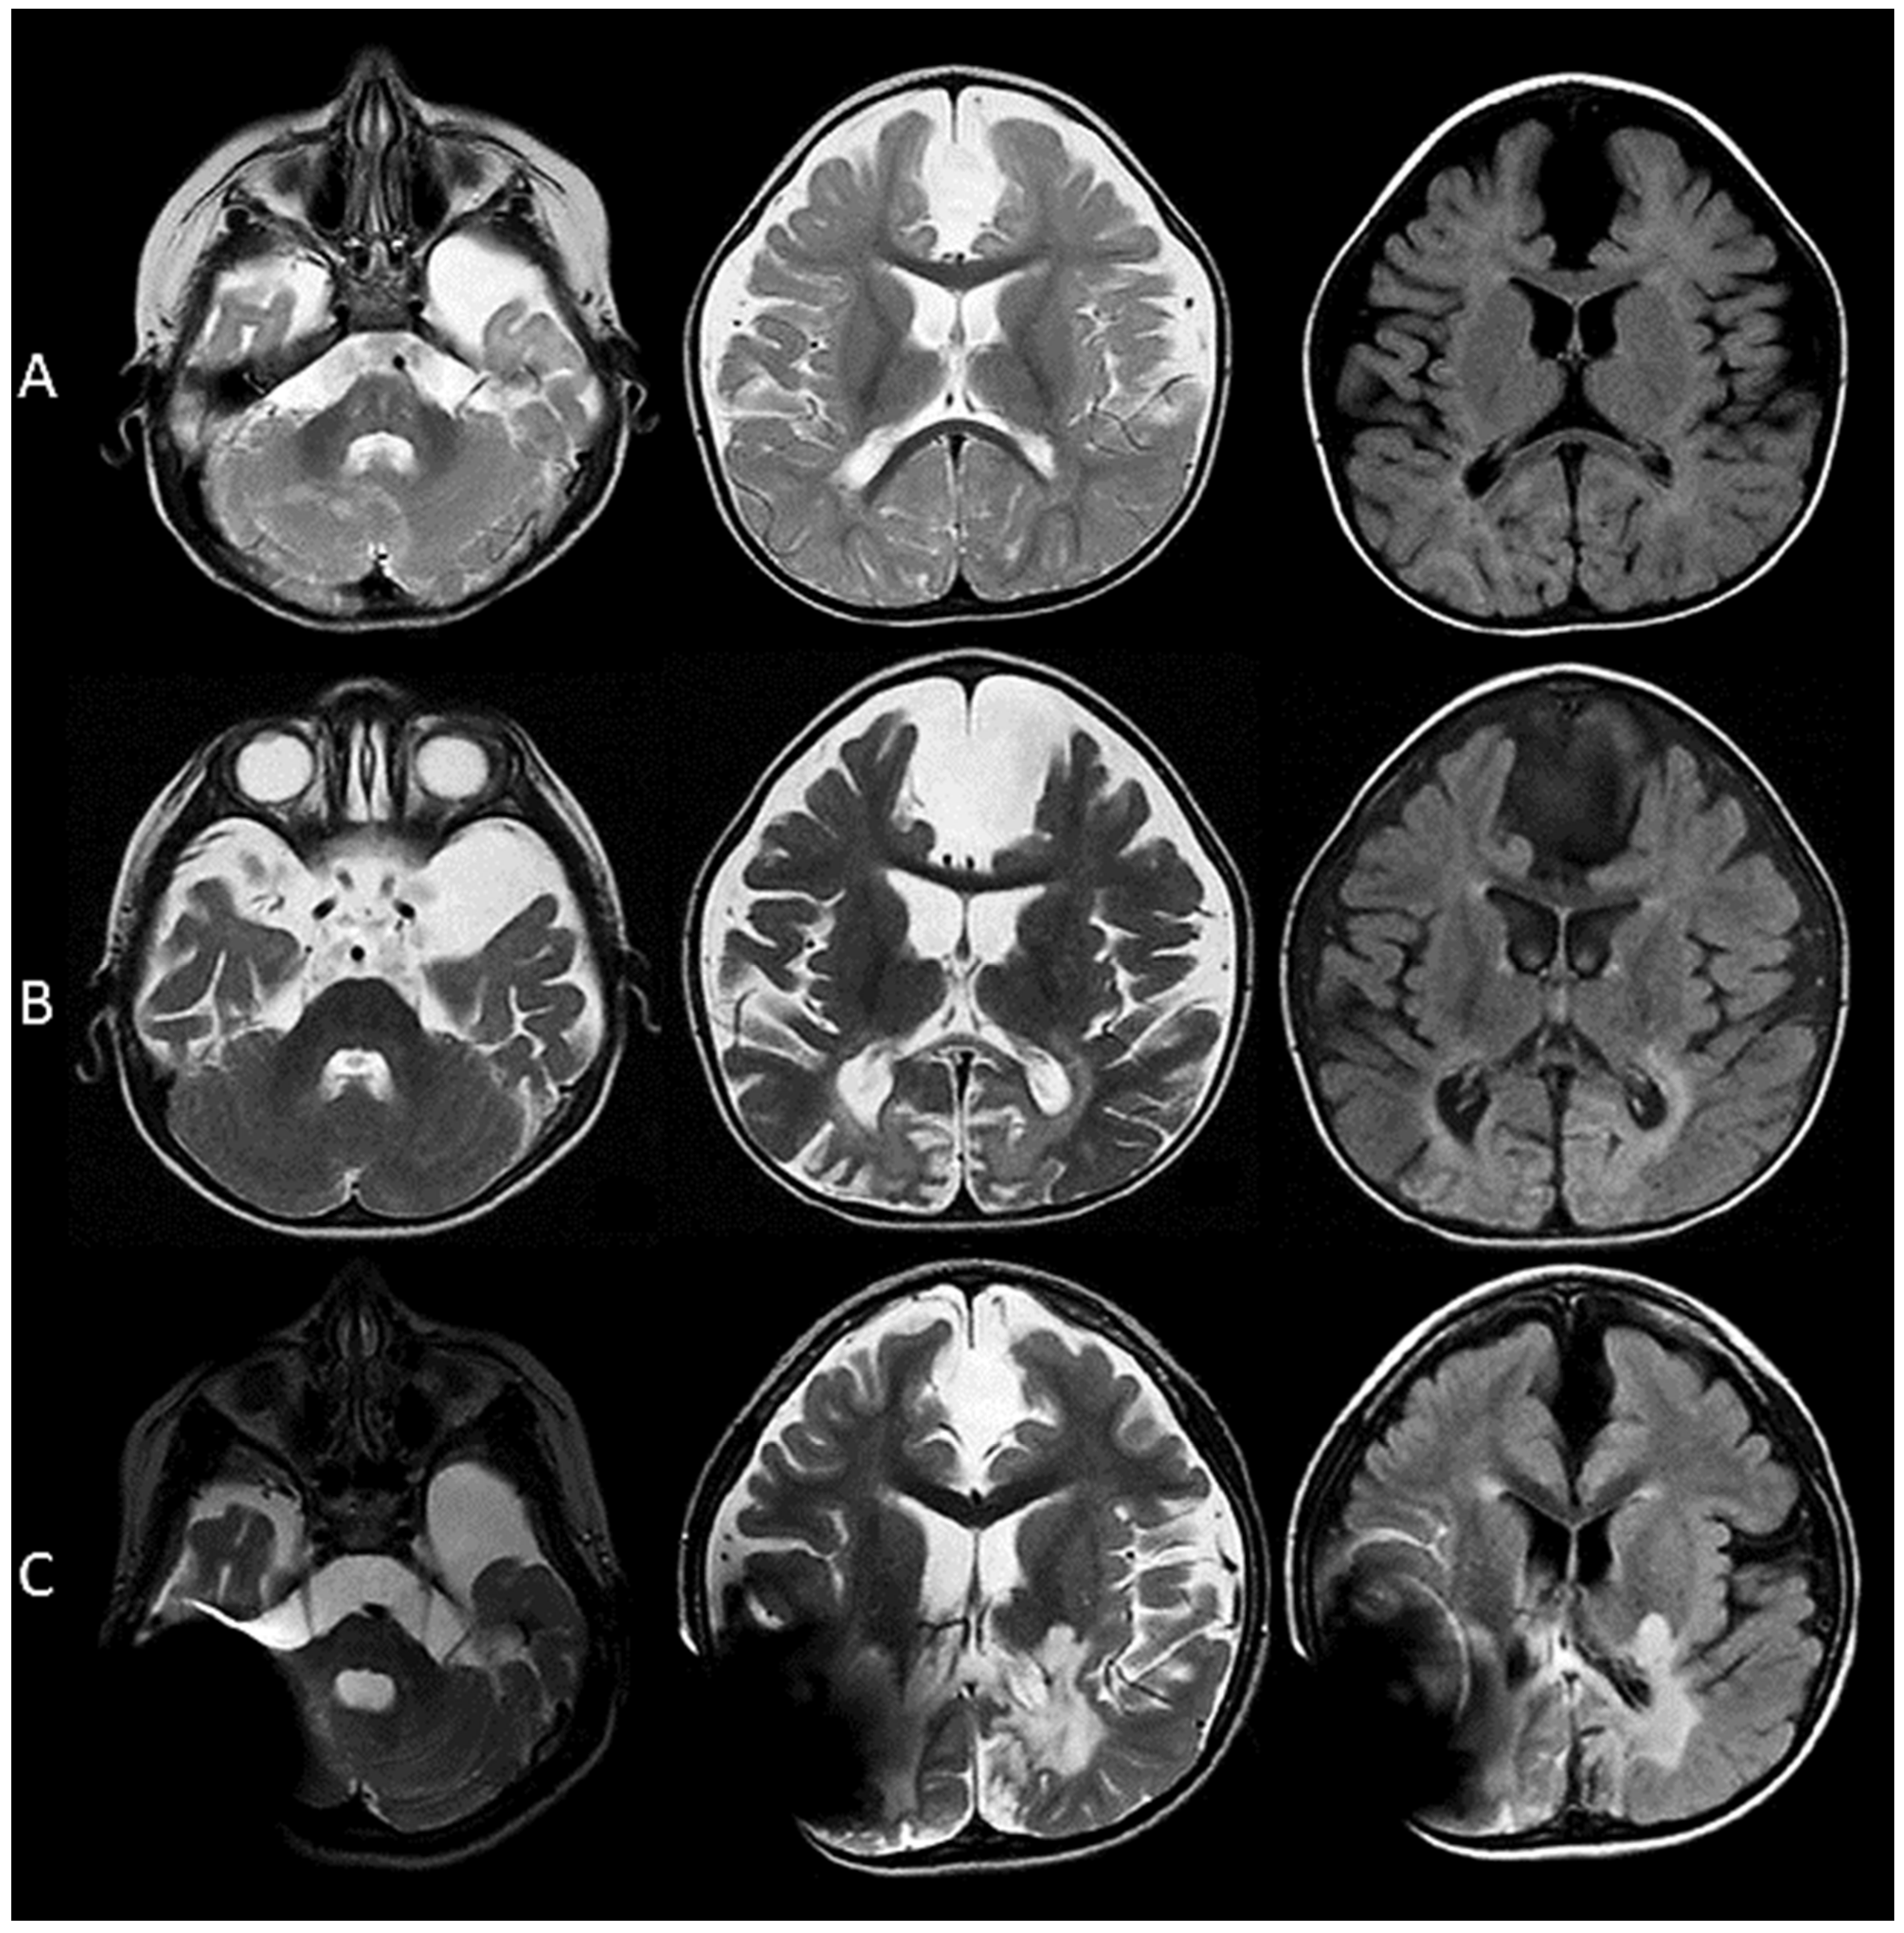

3.1.3. Images